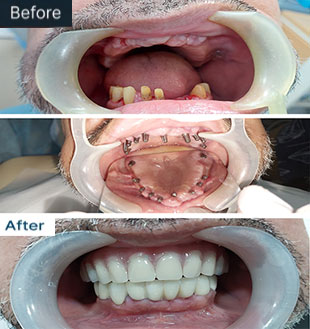

Don't Just Take Our Word For It,

Check Out These Incredible Results

From Our Patients!